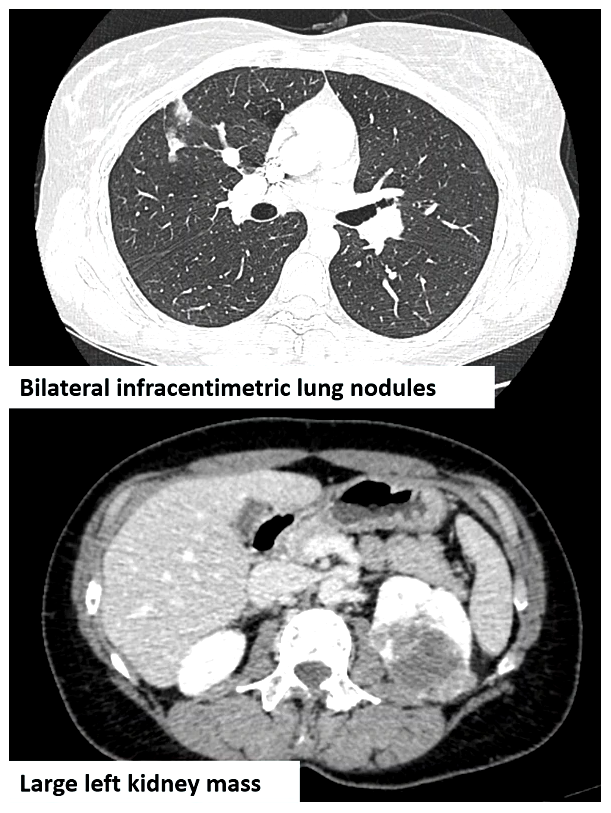

Prof. Flippot proceeded to describe what was seen in the CT scan (see image): primary lung metastasis, a small abundance of haemoptysis, the nodules were in the proximity of major vessels in the lung, and the primary tumour was asymptomatic. He asked the panel if the primary tumour should be removed. Urologist and Chair of Plenary Session 8, Prof. Axel Bex (GB) opted for systemic therapy. Medical oncologist Dr. Laura Marandino (GB), radiation oncologist Prof. Ben Vanneste (NL), and urologist Dr. Wolfgang Loidl (AT) agreed.